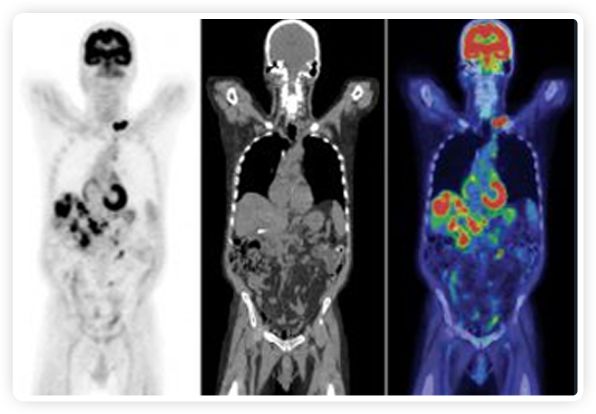

PET+放療共同治療

RefleXion將PET成像與立體定向放射治療相結(jié)合。在注射示蹤劑后,RefleXion的技術(shù)基于示蹤劑信號(hào)實(shí)時(shí)地在一個(gè)或多個(gè)目標(biāo)上引導(dǎo)治療性X射線。使用這種專(zhuān)有方法,RefleXion的平臺(tái)有可能比現(xiàn)有系統(tǒng)向癌癥病變提供更高劑量的輻射,并改善周?chē)】到M織的保護(hù)。

為了避免PET長(zhǎng)圖像采集時(shí)間,RefleXion開(kāi)發(fā)了一項(xiàng)專(zhuān)利技術(shù)使用重合的PET光子對(duì)來(lái)指導(dǎo)放射治療束,因?yàn)閷?shí)時(shí)檢測(cè)發(fā)射的光子,為生物指導(dǎo)提供了一種時(shí)間有效的方法。